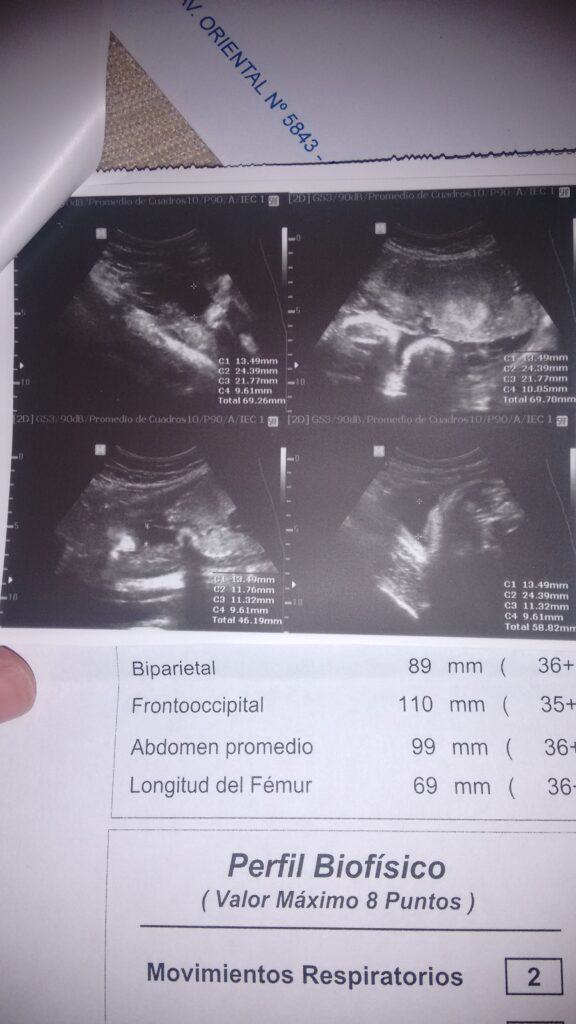

en fin hasta hoy a mi bebé le faltan 4 días para nacer, aspiro y espero todo me salga bien deseo un parto normal y que todo mejore en mi vida personal, cuando do Nazca mi bebé contaré el siguiente suceso, así no me lean.